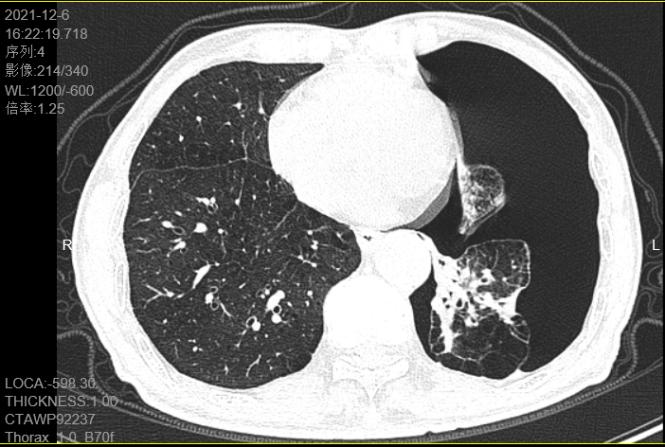

患者黄伯是我院呼吸内科的“常客”,他患有双肺肺气肿、肺大泡,反复发作自发性气胸,稍不留意一用力大便或搬动重物就突发气促加重!“肺又爆了,又要去人医5楼住院放管排气了......”,黄伯伯这次端了盆水后又再发气促,于2021年12月6日门诊就诊查胸部CT提示:左侧气胸压缩70%,当天晚上入住呼吸内科后当班医生给予实施“左侧胸腔闭式引流术”,术后黄伯气促很快缓解了。但这次停留胸腔闭式引流管的时间有点长,已经超过大半个月了,水封瓶内还有气泡溢出提示气胸一直没有愈合不能拔管,黄伯心情不免有点焦灼。

治疗前患者左侧气胸